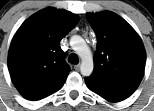

问题 21岁,女,颈部淋巴结肿大,无压痛,请结合CT检查,选出最可能的诊断 ( )

选项 A.淋巴瘤 B.淋巴结核 C.结节病 D.转移性淋巴结肿大 E.间皮囊肿

答案 A